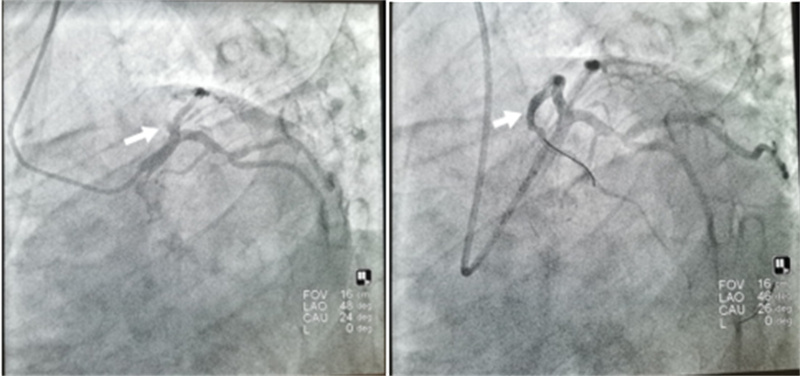

石琳与马斌医生共同为患者进行了冠脉造影检查,术中发现前降支开口100%闭塞并植入支架一枚,从接诊到支架植入仅耗时四十分钟。术后患者恢复良好,目前已康复出院。